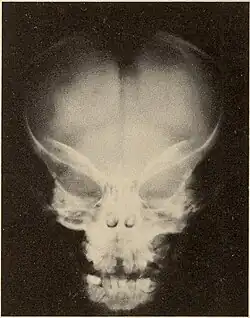

Pycnodysostosis causes the bones to be abnormally dense; the last bones of the fingers (the distal phalanges) to be unusually short; and delays the normal closure of the connections (sutures) of the skull bones in infancy, so that the "soft spot" (fontanelle) on top of the head remains widely open.[9] Because of the bone denseness, those with the syndrome suffer from fractures.[7]

Other abnormalities involve the head and face, teeth, collar bones, skin, and nails. The front and back of the head are prominent. Within the open sutures of the skull, there may be many small bones (called wormian bones). The midface is less full than usual. The nose is prominent. The jaw can be small. The palate is narrow and grooved. There will be delay in fall of milk teeth. The permanent teeth can also be slow to appear. The permanent teeth are commonly irregular and teeth may be missing (hypodontia). The collar bones are often underdeveloped and malformed. The nails are flat, grooved, and dysplastic. High bone density, acro-osteolysis and obtuse mandibular angle are the characteristic radiological findings of this disorder.[10]

Pycnodysostosis is one of those disorders which has a typical facial gestalt[15] and can be clinically identified in the majority of cases. Skeletal surveys can also aid in clinical diagnosis and characteristic features include high bone density, acro-osteolysis and obtuse mandibular angle. Molecular testing will be the final resort to confirm the diagnosis. Due to the limited number of exons of the CTSK gene that causes pycnodysostosis, a cheaper genetic testing called Sanger sequencing can be employed to confirm the diagnosis.

Differences from osteopetrosis

Many of the radiological findings of PYCD are similar to those of osteopetrosis, a disease that causes increased bone density due to a defect in bone reabsorption; however, the two diagnoses differ in several ways.[16][17] In PYCD, there is also:[17]

- Wormian bones

- Delayed closure of sutures and fontanels

- Obtuse mandibular angle